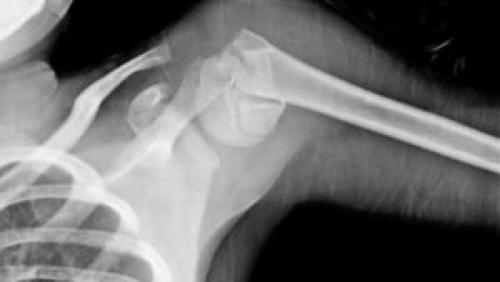

Реабилитация после перелома большого бугорка плечевой кости. Что такое перелом большого бугорка плечевой кости, приводим примеры

Травму плечевой кости с переломом бугорка считают достаточно редкой.

От своевременной и точной диагностики, тактики лечения зависят правильное функционирование сустава плеча, снижение риска получения пациентом инвалидности.

Виды перелома

На основе данных осмотра врача, изучения показаний рентгенограммы, МРТ проводится адекватная диагностика, определяется тактика лечения. Раннее обращение потерпевшего содействует предотвращению осложнений после травмы.

Принято различать три вида перелома:

- контузионный (результат прямого воздействия силы);

- отрывной, без смещения;

- отрывной, со смещением.

Особенность контузионной формы — в осколочном либо вколоченном характере, когда бугорок под влиянием агрессивной силы входит в ткани кости.

Отрывные переломы связаны с мышечным сокращением, вследствие которого происходит смещение бугорка. Если воздействие слабое, смещение не происходит, остается повреждение кортикального слоя. Причиной отрыва могут быть непрофессиональные действия по вправлению вывиха плеча, приложению чрезмерных усилий.

Большинство переломов носит закрытый характер.

Открытая форма встречается редко, но она несет опасность инфицирования, риск развития остеомиелита.

Характер лечения зависит от разновидности перелома и индивидуальных особенностей организма пострадавшего. Первичная медицинская помощь — в обезболивании пострадавшего. Далее проводится осмотр больного и аппаратное исследование для правильной постановки диагноза.